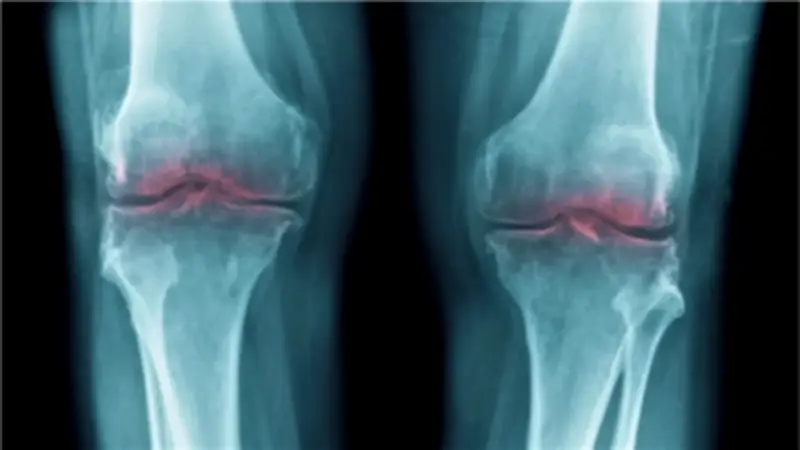

كشفت دراسة علمية حديثة عن اكتشاف ثوري يمكنه تجديد الغضروف التالف وعلاج آلام المفاصل، مما يمنح أملاً جديداً لملايين المصابين بالتهاب المفاصل حول العالم. وأظهرت الأبحاث أن فقدان الغضروف المرتبط بالتقدم في العمر يعود إلى بروتين واحد، مما يفتح الباب أمام علاجات مستقبلية قد تعيد الحركة وتخفف المعاناة لدى كبار السن.

خلال التجارب، تم إدخال مثبط لإنزيم بروتين 15-PGDH إلى فئران مسنة، مما أدى إلى زيادة سمك غضروف الركبة الذي كان قد تآكل سابقاً. وفي تجارب مماثلة على فئران صغيرة مصابة، وفر المثبط حماية فعالة ضد الأعراض النمطية لالتهاب المفاصل الناتج عن الإصابات.